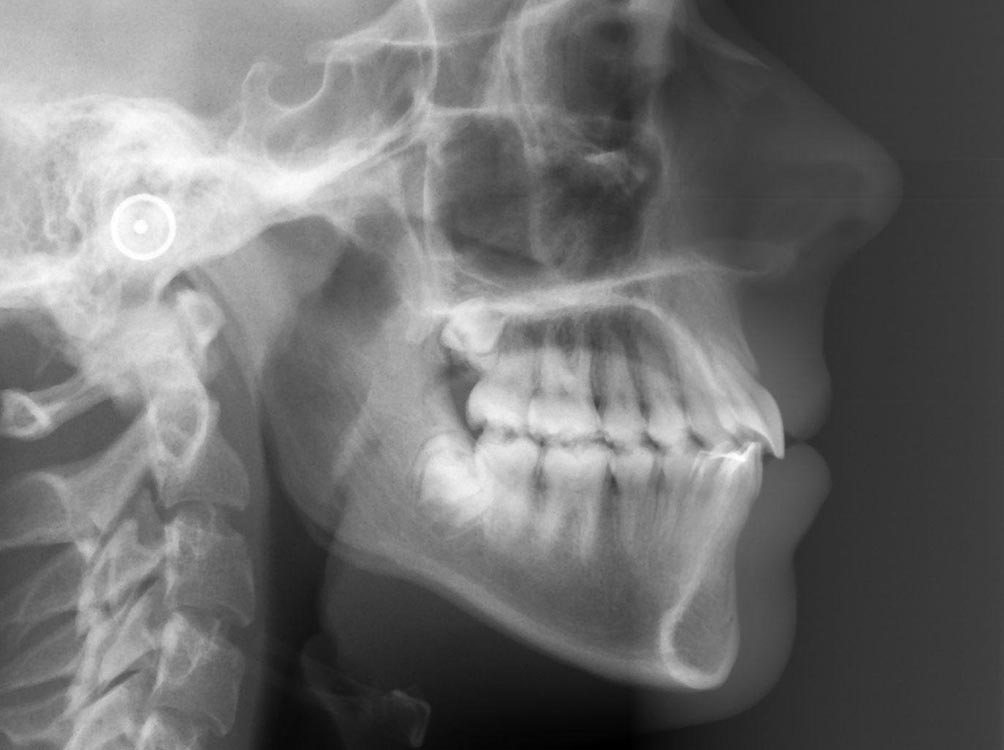

En muchas ocasiones observamos por medio de radiografías tridimensionales como los escáner CBCT o a simple vista en intervenciones quirúrgicas, la ausencia de hueso en los dientes o alrededor de los implantes.